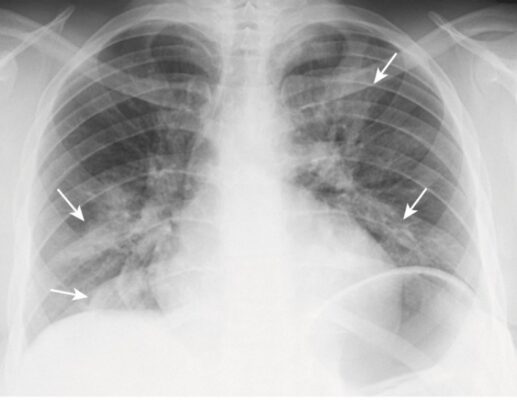

- Vi sinh vật nguyên mẫu gây ra viêm phổi hang là vi khuẩn lao (Mycobacterium tuberculosis).

- Tạo hang thường gặp trong lao hậu tiên phát (lao tái hoạt) nhưng hiếm gặp ở lao nguyên phát. Các hang thường nằm ở các thùy trên, hai bên và có thành mỏng, bờ trong nhẵn và không chứa mức dịch – khí (Hình 7). Sự lây lan xuyên phế quản (từ một thùy trên sang thùy dưới bên đối diện hoặc đến một thùy khác trong phổi) sẽ khiến bạn nghĩ đến nhiễm khuẩn Mycobacterium tuberculosis.